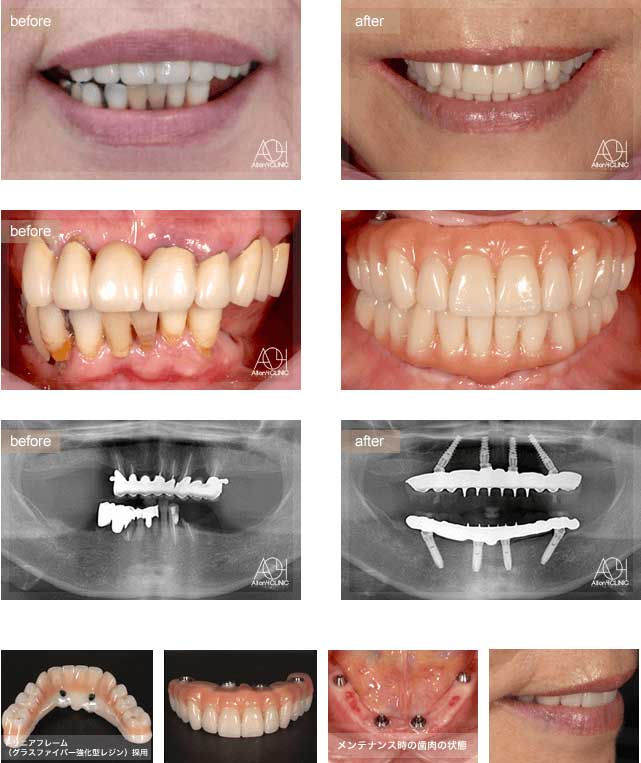

インプラント症例Implant Case

前歯のインプラント症例#8

| 治療内容 | インプラント埋入 |

| 費用 | 2,332,000円(税込) |

| リスク | インプラントは、過剰な咬合力がかかった場合、インプラント周囲炎により骨の吸収を認めることがあります |